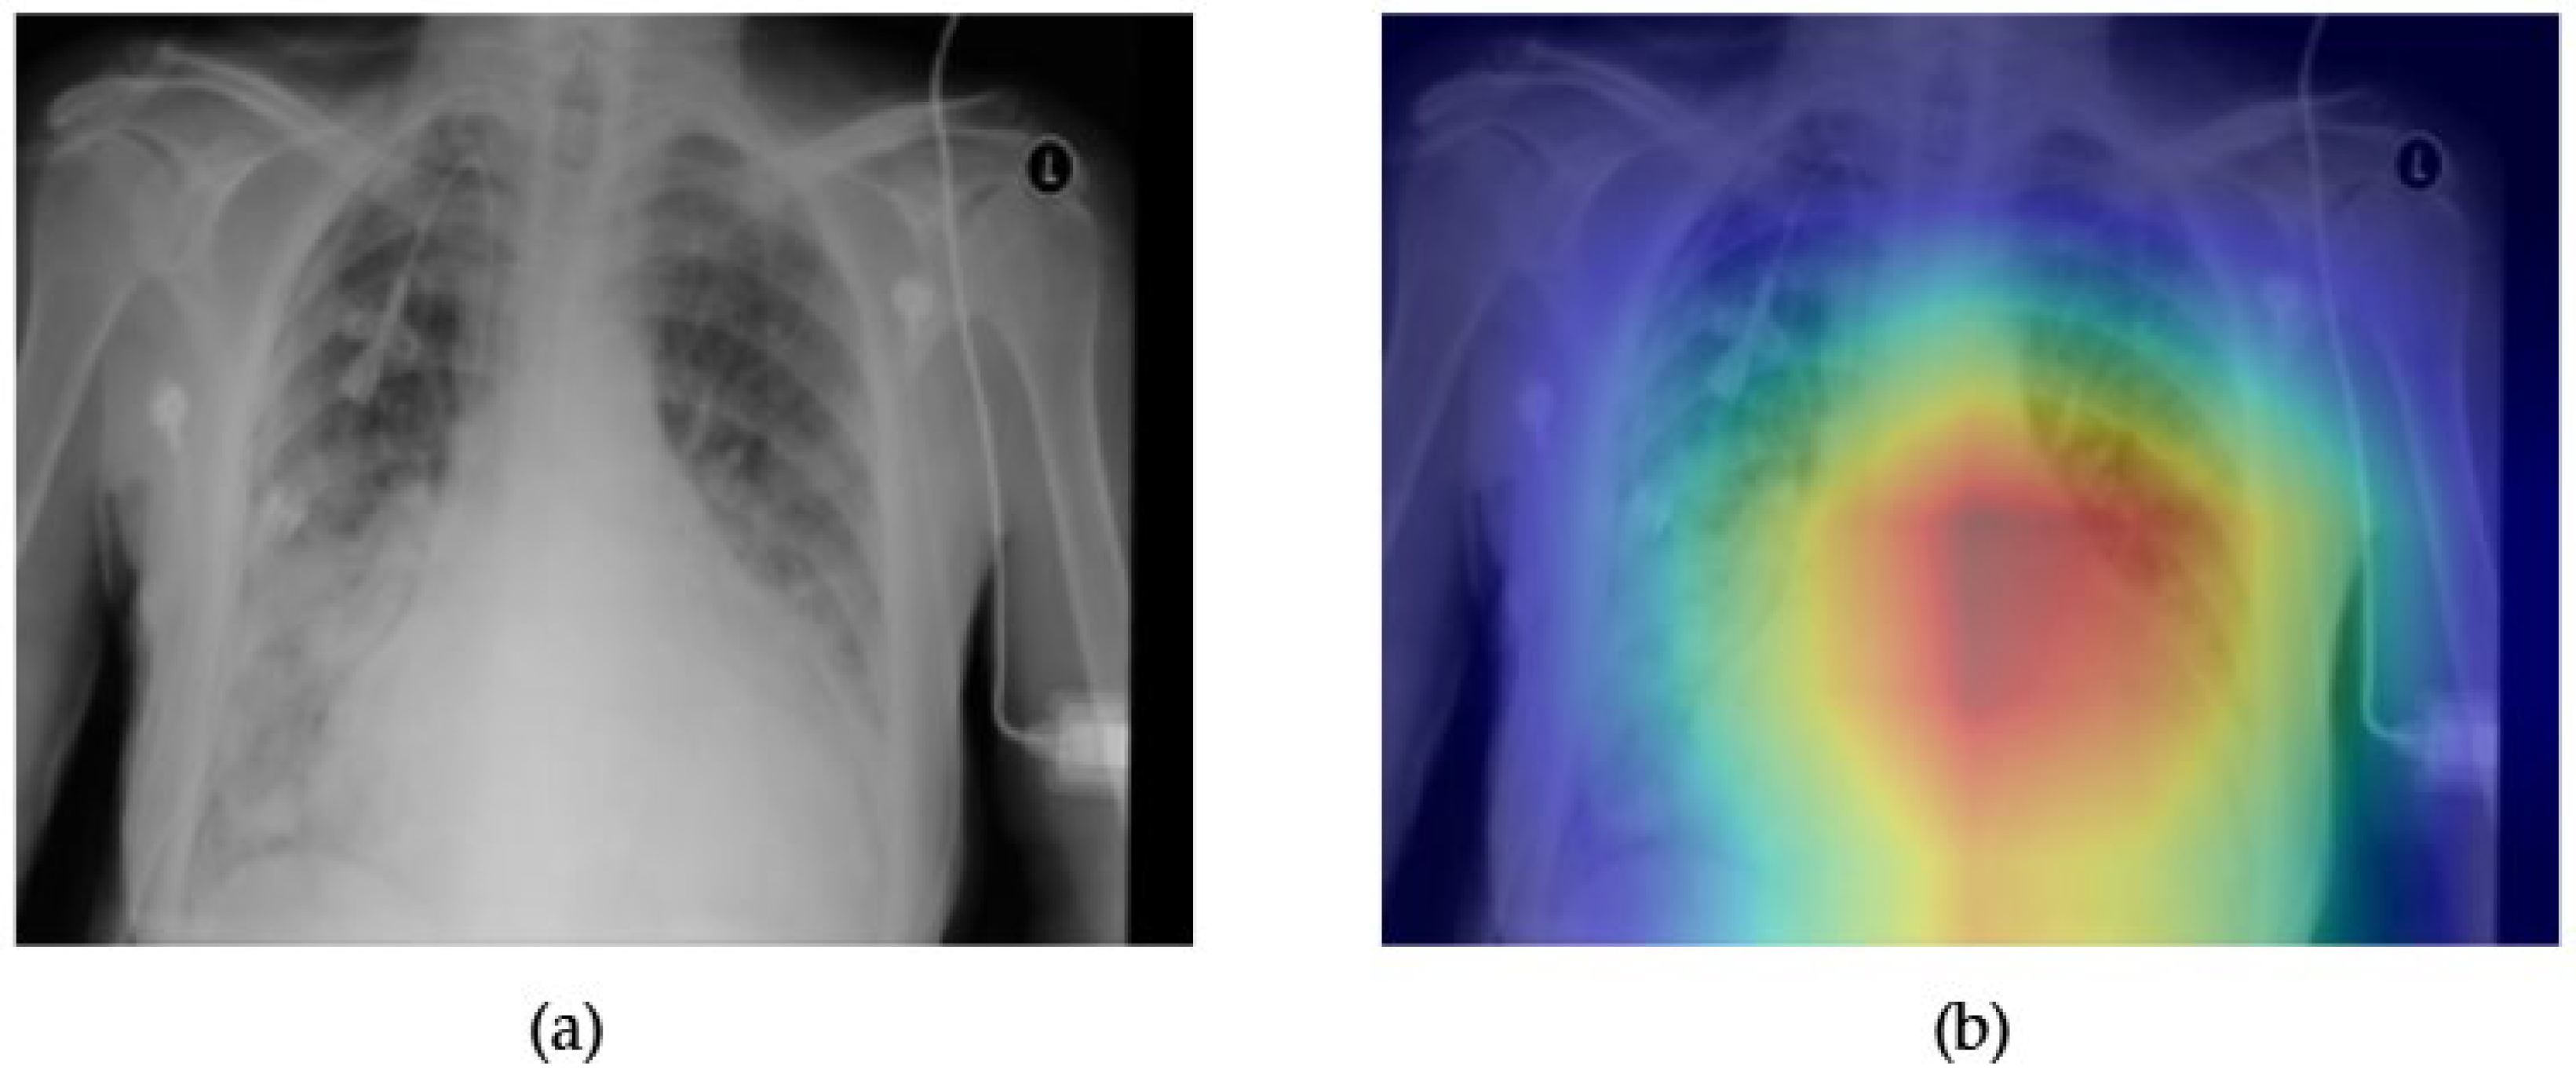

- Although our Grad-CAM-based explainability provides useful localization cues, it is inherently limited by its post hoc nature and reliance on gradient flow from the final convolutional layers. Future research could incorporate advanced interpretability techniques such as Layer-wise Relevance Propagation (LRP), Integrated Gradients, or attention rollouts in Transformers, which may offer a more complete understanding of model reasoning.